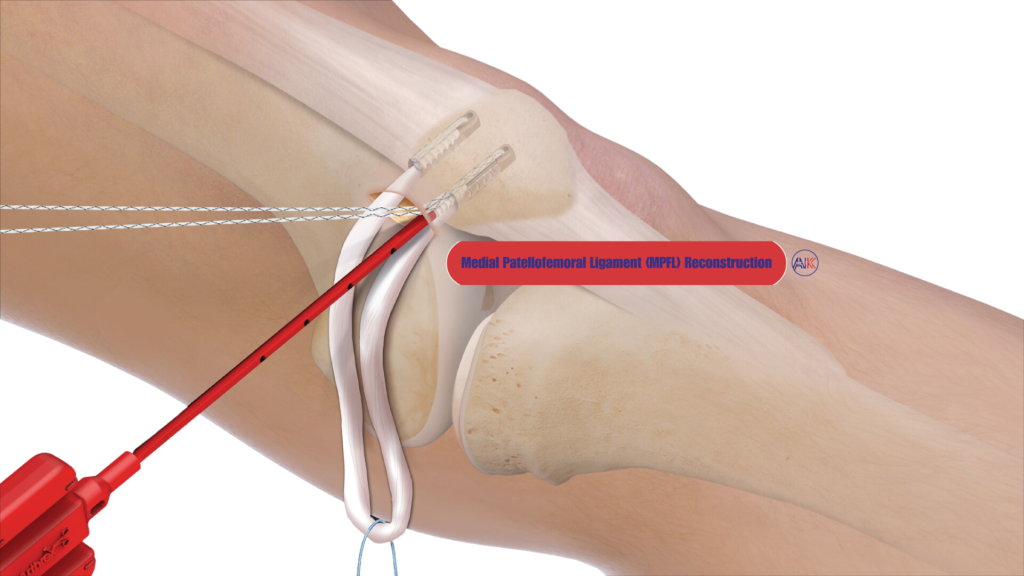

Medial Patellofemoral Ligament (MPFL) Reconstruction

The MPFL is a crucial ligament that helps keep your kneecap in its proper position. If it has been damaged or stretched due to repeated dislocations, reconstruction may be necessary to restore stability to your kneecap.